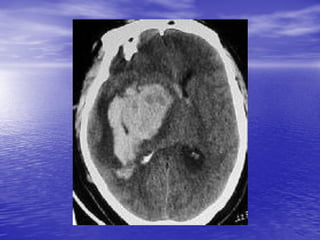

This document discusses the management of intracranial pressure and cerebral edema in neurocritical care patients. It covers topics such as how patients typically present with brain injuries, important caveats in neurological examinations, principles of cerebral resuscitation, mechanisms of primary and secondary brain injury, the pathophysiology over time, imaging techniques including CT scans and MRI, monitoring techniques like intracranial pressure monitoring, and treatment approaches like the use of hyperosmolar therapy with mannitol or hypertonic saline. The goal is to prevent secondary brain injury after the initial primary injury occurs.